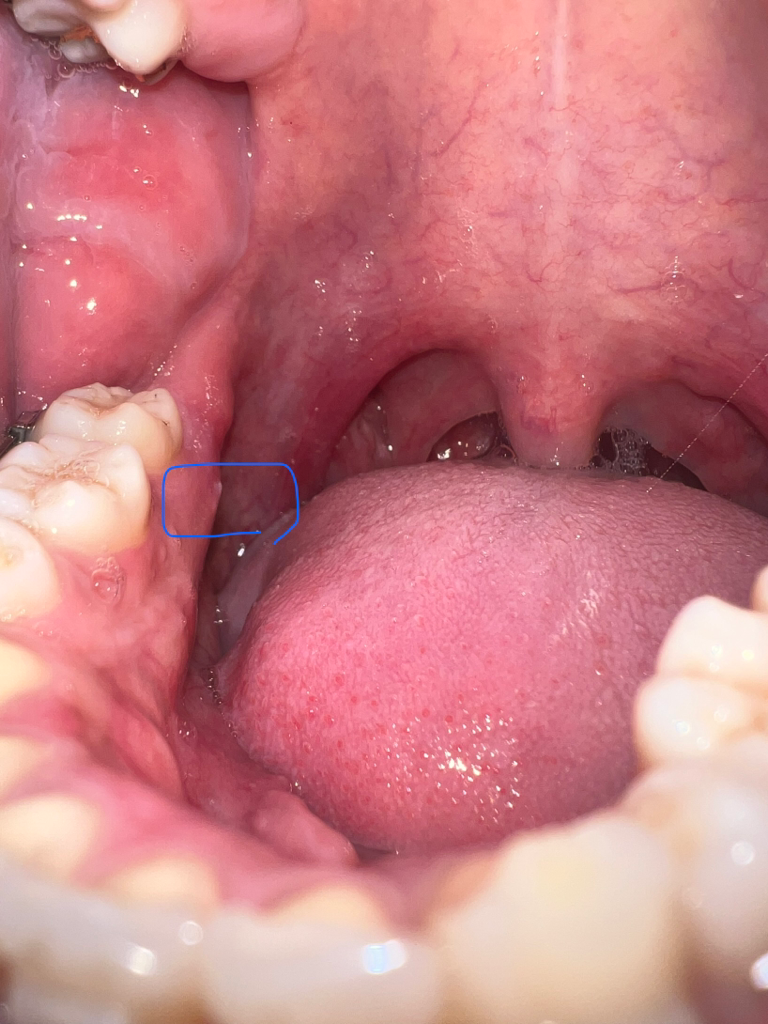

안녕하세요 한달전에 어금니 안쪽에서 이물감이 들더니 뭐가 튀어나와 찾아보니 뼈가 튀어나오는거라거 하더라구요 그러다가 한 2주전부터 슬슬 통증이 얼얼한? 묵직한 통증이 미미하게 있더라구요 ㅠ 밥먹을때나 찬물 뜨거운물엔 이상은 없는데 그냥 저기를 누르면 아파요 ㅠ 그러다가 흰색 튀어나온 부분에서 고름같은게 나와서 너무 당황스러워서 치과에 방문해서 진찰을 받으니 뼈가 튀어나온게 맞다고 하더라구요 ㅠ 그리고 치근단 엑스레이도 촬영해서 치아쪽 이상이 아니라 잇몸 궤양이 일어난거같다고 항생제랑 소염진통제 5일치 처방해줬어요.. 약먹고나서 3일정도 됐는데 고름은 이제 눌러도 안나오는데 통증은 뭔가 그대로인 느낌이에요 혀나 손으로 누르면 통증이 있어요 ㅠㅠ 턱관절에도 이상이 있는거같긴한데.. 확실히 여기 이 튀어나온 부분을 누르면 통증이 있는건 맞는거같아요 ㅠ 혹시 이거 큰병인지 너무 걱정되서 글 써봅니다 의견 부탁드립니다 선생님들!